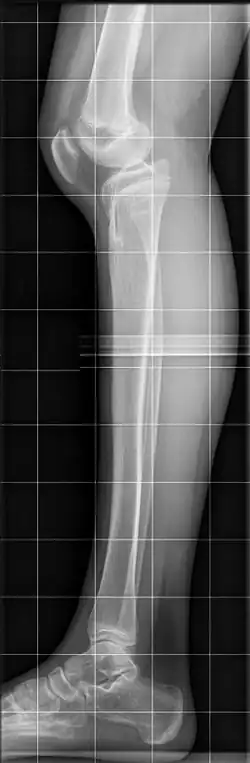

Das Genu recurvatum ist ein abnorm überstreckbares Knie. Während gesunde Erwachsene das Knie normalerweise in der Neutral-Null-Methode bis in 0-Stellung strecken können, gilt bei Kindern eine Überstreckbarkeit bis 10° als physiologisch, ab 15° als krankhaft.[2][3][4]

Die Fehlstellung kann bereits vorgeburtlich mittels Feinultraschall erkannt werden.[9] Die Diagnose ergibt sich bei der körperlichen Untersuchung, die Abklärung der Ursache erfolgt durch eine Röntgenaufnahme vorzugsweise belastet (im Stehen).[3][7] Normalerweise ist das Tibiaplateau nach dorsal (hinten) um 7–10° geneigt, beim Genu recurvatum ist diese Neigung vermindert, aufgehoben oder nach ventral abgeflacht.[8][2]